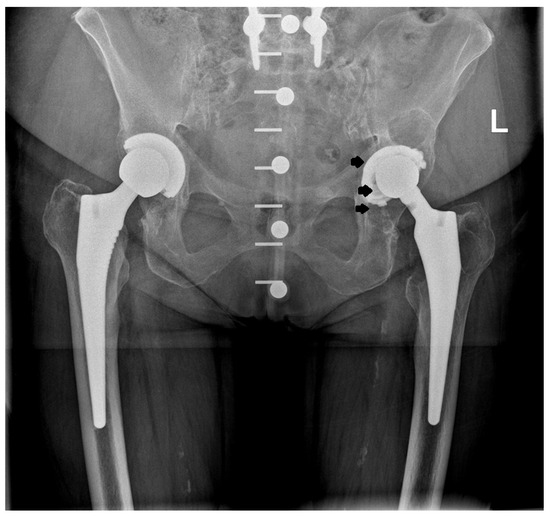

2.2. Design of the L-Cup Acetabular Component

3. Results

4. Discussion